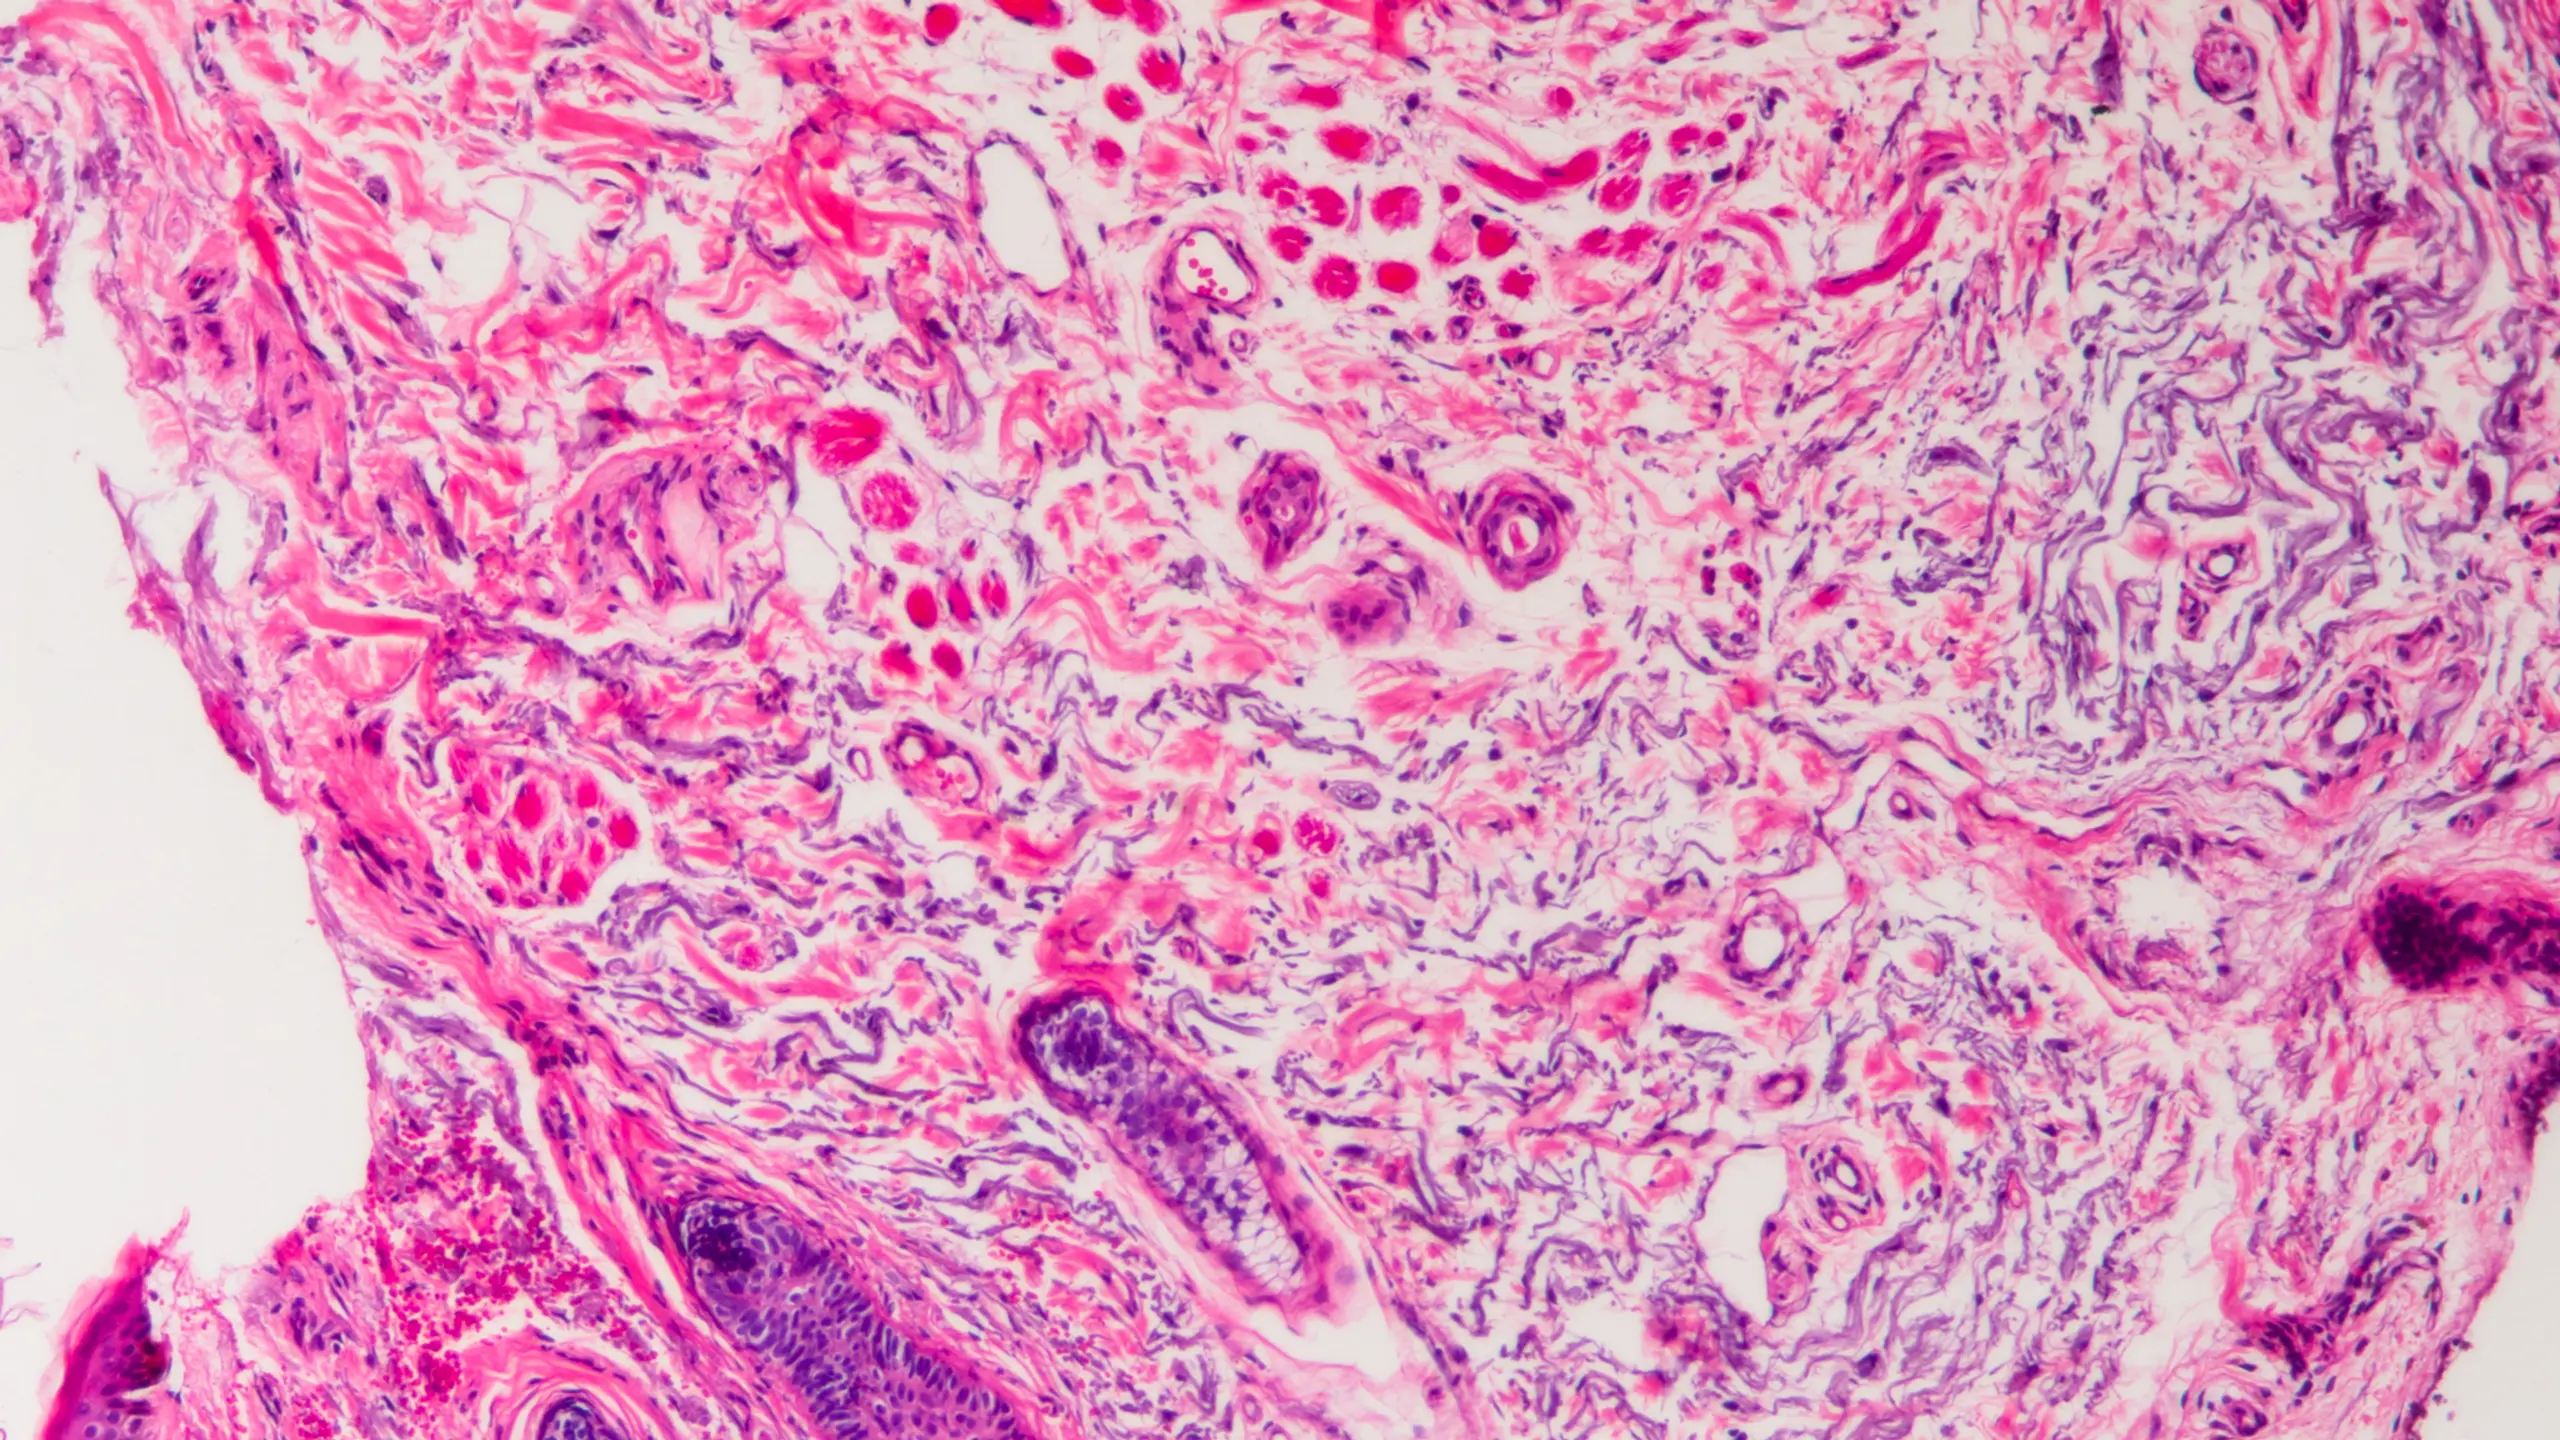

Noch ungeahnte Möglichkeiten birgt die künstliche Intelligenz, die aber, wie Zielinski sicher ist, "die Krebsmedizin revolutionieren wird". Ob in der Diagnostik, bei Röntgenuntersuchungen, Medikamentenwicklung oder bei der Typisierung von Gewebe: "Mittels KI lassen sich Gewebeschnitte innerhalb weniger Sekunden mit Millionen anderen Gewebeproben in Archiven der ganzen Welt vergleichen", so der Experte. "Was deren Interpretation noch genauer machen wird. Schon in naher Zukunft können Gewebeschnitte noch während Krebsoperationen genau analysiert werden – ein großer Fortschritt für die Chirurgie."